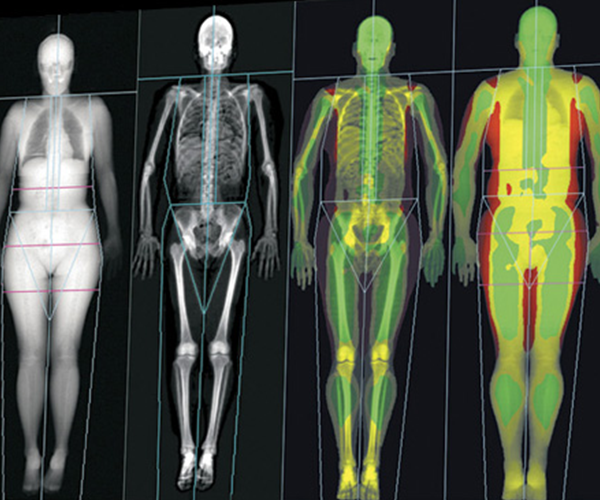

La Unitat de Metabolisme Mineral i Ossi és un servei especialitzat en el diagnòstic, tractament i seguiment de trastorns relacionats amb el metabolisme dels minerals i la salut òssia. Aquesta unitat aborda principalment patologies com l’osteoporosi, el raquitisme, l’osteomalàcia, i altres malalties que afecten la densitat i estructura òssia, així com desequilibris en els nivells de calci, fòsfor i vitamina D. També tracta condicions metabòliques relacionades amb les glàndules paratiroides i altres disfuncions endocrines que poden comprometre la salut dels ossos. L’objectiu és prevenir fractures i mantenir la qualitat de vida del pacient.